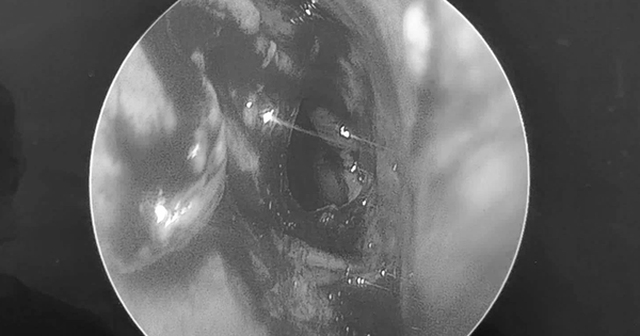

Sau khi thăm khám, bác sĩ Nguyễn Thanh Tiên cùng ê kíp đã tiến hành phẫu thuật mở xoang bướm và lấy sạch bệnh tích, dẫn lưu bằng phương pháp nội soi mũi xoang.

Đáng chú ý, sau phẫu thuật sức khỏe bệnh nhân ổn định, bệnh nhân bắt đầu cảm nhận ánh sáng, phân biệt được bóng người, sụp mi cải thiện dần.